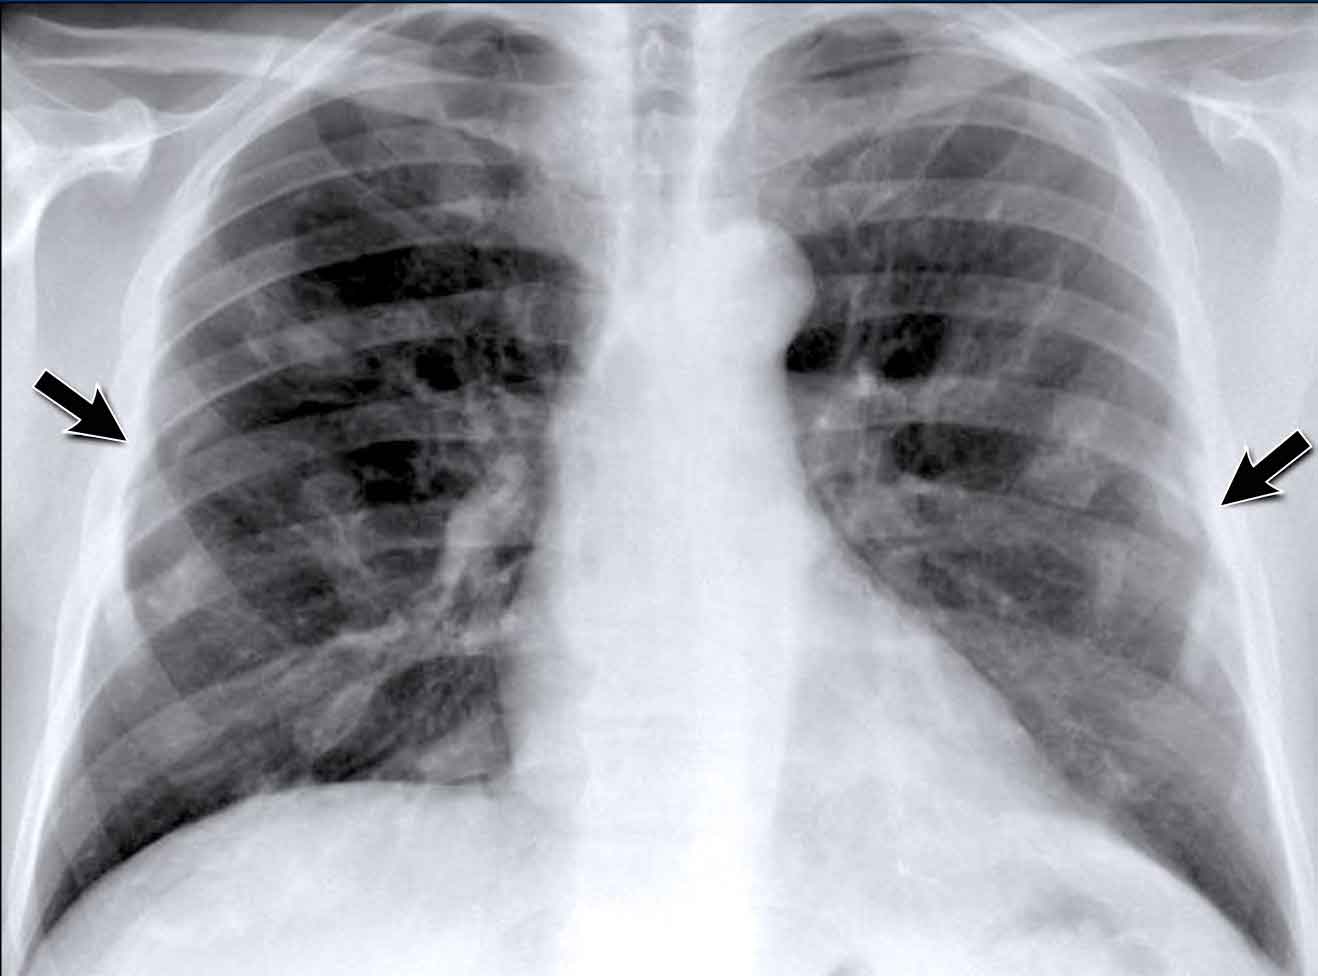

Left Atrial Enlargement

• Patient with a history of chronic mitral valve disease and valve replacement.

• Extreme dilation of the LA leads to bulging of both the right upper cardiac contour (black arrows) and posterior heart border on lateral view (blue arrow).